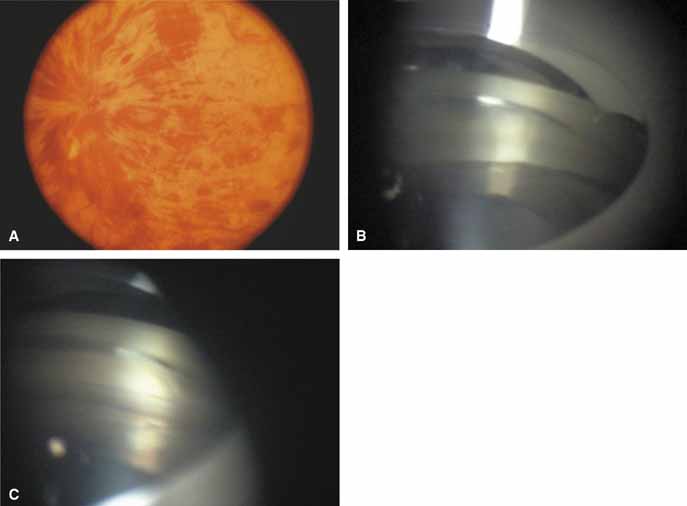

Over the past two decades silicone oil (dimethylpolysiloxane) has enjoyed a resurgence in the repair of complicated retinal detachments. In 1967, Watzke36 found no pressure elevation attributable to silicone but described droplets in the superior angle that result from silicone's lower specific gravity (buoyancy) compared with water. Silicone-induced glaucoma does occur, however, and one possible mechanism is an acute pupillary block due to the buoyancy of the silicone sometimes combined with overfilling the aphakic eye (Fig. 5). This can be averted by performing an inferior iridectomy and by paying careful attention to the silicone volume injected. A second mechanism involves chronic obstruction of an open angle by emulsified silicone microbubbles (more likely with low viscosity silicone, 1,000 centistokes, than high viscosity silicone, 12,500 centistokes) (Fig. 6), pigmented cells, and silicone-laden macrophages or silicone-induced fibrosis of the trabecular meshwork due to possible inherent fibrogenicity of this compound.37,38 Treatment of this open-angle glaucoma is generally medical, although silicone removal may be required. Although some studies have confirmed the presence of emulsified oil in the anterior chamber as a strong predictor of pressure elevation, others do not, suggesting that multiple factors are at play.39,40,41,42 Often this can only be seen on gonioscopy, and removal of the oil, if possible, is beneficial in some cases. Sometimes an expected pressure elevation that would otherwise occur may be muted by concomitant cyclitic membrane formation or hypotony associated with recurrent retinal detachment. The use of shunt procedures in this difficult glaucoma has led to the unusual complication of silicone oil escape into the subconjunctival space43,44 (Fig. 7). Whether placed superiorly or inferiorly, shunts should probably be avoided in these eyes unless the silicone oil can first be safely removed. Transscleral diode laser cyclophotocoagulation has been proven to be an excellent noninvasive option in treating these eyes for recalcitrant pressure elevation.45,46

Intravitreal gas has become a standard part of complex and routine retinal repairs. The appropriate use of intraocular long-acting gas tamponades requires a thorough knowledge of the time-expansion characteristics of the chosen gas (sulfur hexafluoride; perfluoropropane) as well as the clinical situation (partial or total fill of the vitreous cavity).47 Sulfur hexafluoride has a peak expansion 6 to 12 hours after injection. A 20% mixture usually represents the concentration that will not expand in volume when a total fill of the vitreous cavity is performed. Perfluoropropane expands acutely over a similar time frame. A 14% mixture with room air represents the “safe” nonexpansile percentage when the total volume is replaced (Fig. 8).